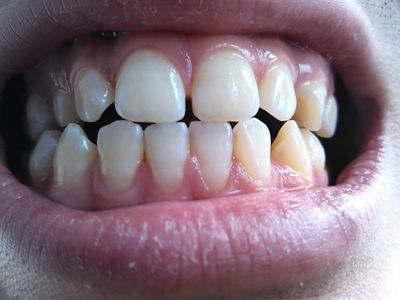

牙龈退缩上下牙的牙根变黄牙缝变大图

牙龈退缩后,上下排的多颗牙齿出现牙龈后退,牙根有较多的暴露,牙体增长明显,牙缝增宽、变大,牙齿表面泛黄。萎缩的牙龈发白或颜色深重呈紫红色,敏感易受刺激。